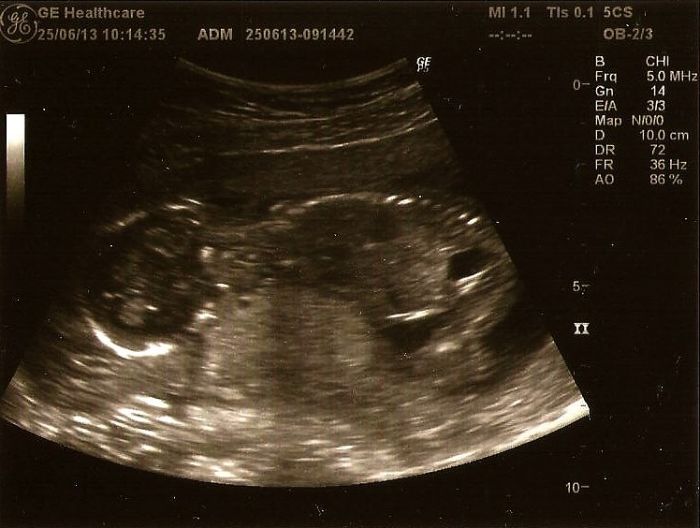

AHoj Afroditko,tak za sebou máme další kontrolu v 18tt a vypadá to že budeme mít taky chlapečka!!

Zatím je vše v pořádku,scr.negativni,riziko downa 1:50 000 a krásně rosteme..Jsem šťastná a věřim že tentokrát bude vše v pořádku..Mrňous dneska celou kontrolu prospal,asi ho to počasí taky unavuje..